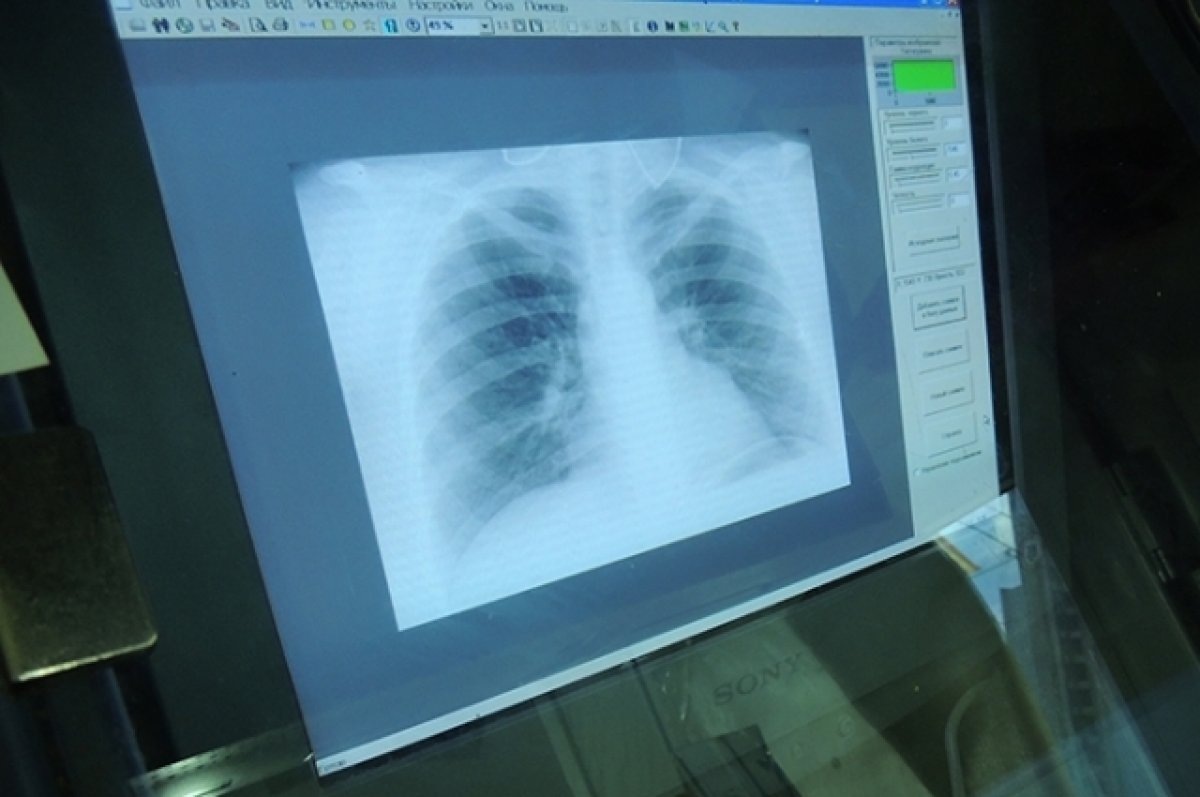

В Медногорске суд удовлетворил иск прокурора о принудительной госпитализации женщины, страдающей заразной формой туберкулеза. Согласно материалам прокуратуры, страдающая туберкулёзом женщина отказывается лечить его в медучреждении. Учитывая высокую степень опасности заболевания, которое в итоге может привести к летальному исходу, уклонение страдающей туберкулезом гражданки от лечения подвергает опасности жизнь и здоровье других людей, затрагивает их права, свободы и законные интересы. На основании этого прокурор обратился в суд с иском о принудительной госпитализации оренбурженки в специализированное медицинское учреждение для обследования и прохождения противотуберкулезного лечения. Требования надзорного ведомства были удовлетворены.